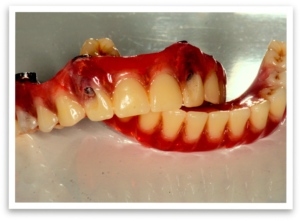

After a thorough examination and discussion, we planned the procedure. A key aspect was the fabrication of an immediate denture in our in-house lab, ensuring Mr. B wouldn’t be without teeth for a single day. We scheduled the procedure and eagerly awaited his new smile.

The day of the procedure arrived. Our team strategically placed four implants each in Mr. B’s upper and lower jaw (maxilla and mandible). The immediate denture was then securely fixed onto the implants, immediately providing him with a functional and aesthetically pleasing smile.